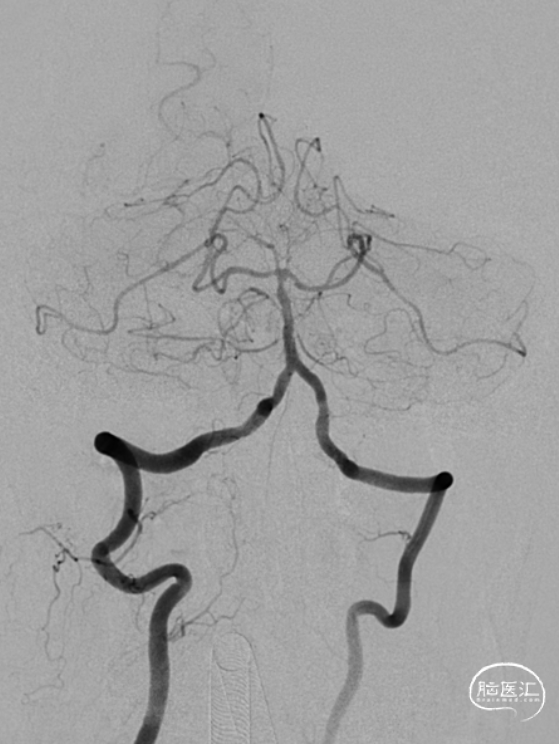

造影示:右侧优势椎,经右侧椎动脉导弯造影,双侧胚胎型大脑后动脉。

术前DSA:双侧后交通动脉开放。

R-CCA

L-CCA

R-VA

L-SUB-VA